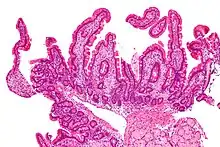

| Low magnification micrograph of Whipple's disease showing the characteristic foamy appearing infiltrate of the lamina propria. Duodenal biopsy. H&E stain. | |

Endoscopy of the duodenum and jejunum can reveal pale yellow shaggy mucosa with erythematous eroded patches in patients with classic intestinal Whipple's disease, and small bowel X-rays may show some thickened folds. Other pathological findings may include enlarged mesenteric lymph nodes, hypercellularity of lamina propria with "foamy macrophages", and a concurrent decreased number of lymphocytes and plasma cells, per high power field view of the biopsy.